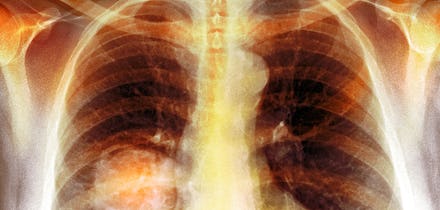

Thanks to Cuba, a revolutionary treatment for lung cancer, the second most common cancer, could potentially stop the disease from being fatal.

Cimavax doesn't prevent lung cancer. However, it stops the disease's spread by attacking a protein involved in the cancer's growth. This has the potential to transform advanced-stage lung cancer into a chronic, treatable condition rather than a fatal one.